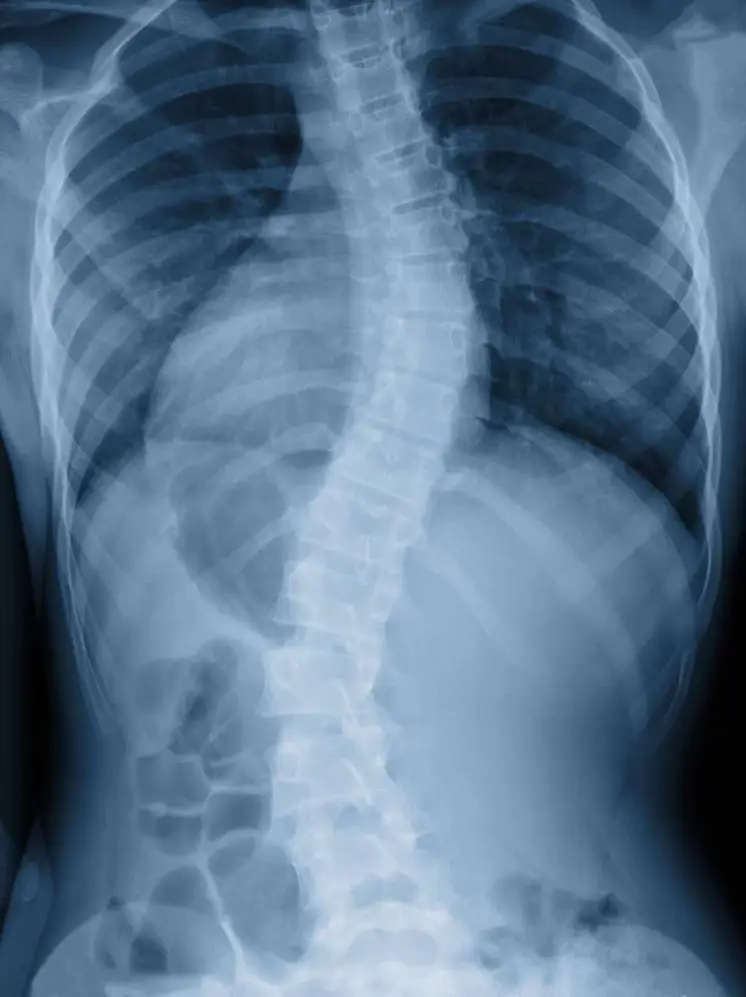

๐Ÿ’ก What Is Scoliosis?

Scoliosis is a condition where the spine curves sideways, often in an โ€œSโ€ or โ€œCโ€ shape. It can be: